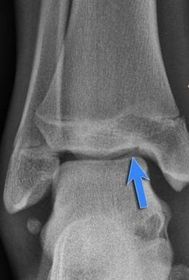

What disease is this? What does the arrow indicate? | Rheumatoid arthritis. Arrow = Bone erosion secondary to inflammation of retrocalcaneal bursa. |